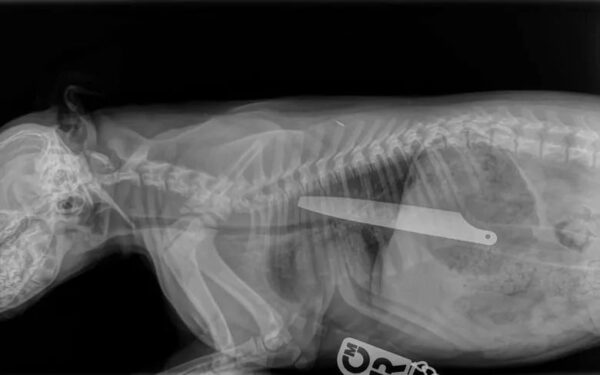

RTG stafika z nożem w brzuchu

Ten stafik miał w brzuchu… 20-centymetrowy nóż!

Wymioty, krztuszenie się, i wreszcie krew z nosa – z takimi objawami Irene Paisley przywiozła swoją 12-tygodniową suczkę Macie do lecznicy...